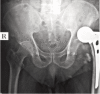

Background and objective: Intracapsular femoral neck fractures are common in the elderly population. To avoid the poor outcome of internal fixation and for early mobilization, hemiarthroplasty is performed. However, there is inadequate evidence to support the choice between unipolar or bipolar hemiarthroplasty. The aim of this study was to compare the outcome of unipolar with the bipolar prosthesis in geriatric patients.

Methods: Forty-one patients above 60 years of age and an acute displaced fracture of the femoral neck were randomly allocated to treatment by either unipolar or bipolar hemiarthroplasty, in the Department of Orthopaedics, between September 2009 and October 2012. Functional outcome was assessed and compared using Harris hip score and radiological parameters with a follow-up of one year.

Results: The two groups of patients with mean age of 67.3 in bipolar group and 75.6 in unipolar group did not differ in their pre-injury characteristics and perioperative parameters. The mean Harris hip score in bipolar and unipolar groups was 86.18±12.18 and 79.79±15.55, respectively (p=0.183); range of motion was 210.63±28.39 and 181.58±37(p=0.015) with bipolar and unipolar groups, respectively. Functional activities were better in the bipolar group. Complications like painful hip, posterior dislocation, periprosthetic fracture and acetabular erosion were encountered in unipolar prostheses.

Conclusion: The use of bipolar endoprosthesis in the management of displaced femoral neck fractures in the elderly was associated with better mean Harris hip score and incidence of complications was limited. Hence, bipolar would be a better option in elderly patients with fracture neck of femur.